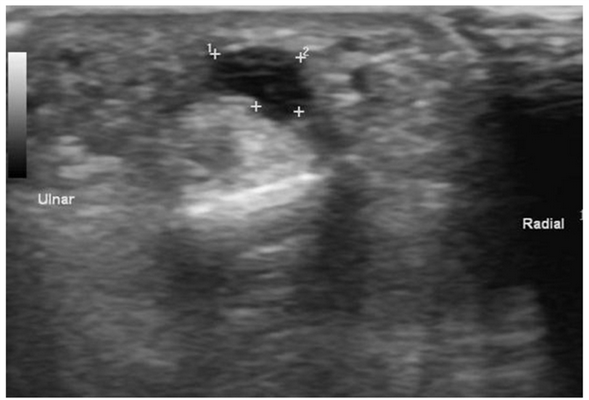

На УЗИ ганглий выглядит как одно- или многокамерное образование с тонким «ободком» и множественными перегородками, чаще всего анэхогенное, реже с эхогенными включениями. Может обнаруживаться также акустическое усиление. Для поиска кровотока в образовании и признаков, позволяющих отличить ганглий от опухоли, используется цветовая или энергетическая допплерография. Ультрасонография, допплерография, МРТ — наилучшие методы визуализации сухожильного ганглия.

Палец - сухожильный ганглий, B-режим

[EN] Эхограмма №685: Сухожильный ганглий на пальце в B-режиме.

Изображение получено с помощью УЗ сканера RS80 (есть в продаже).